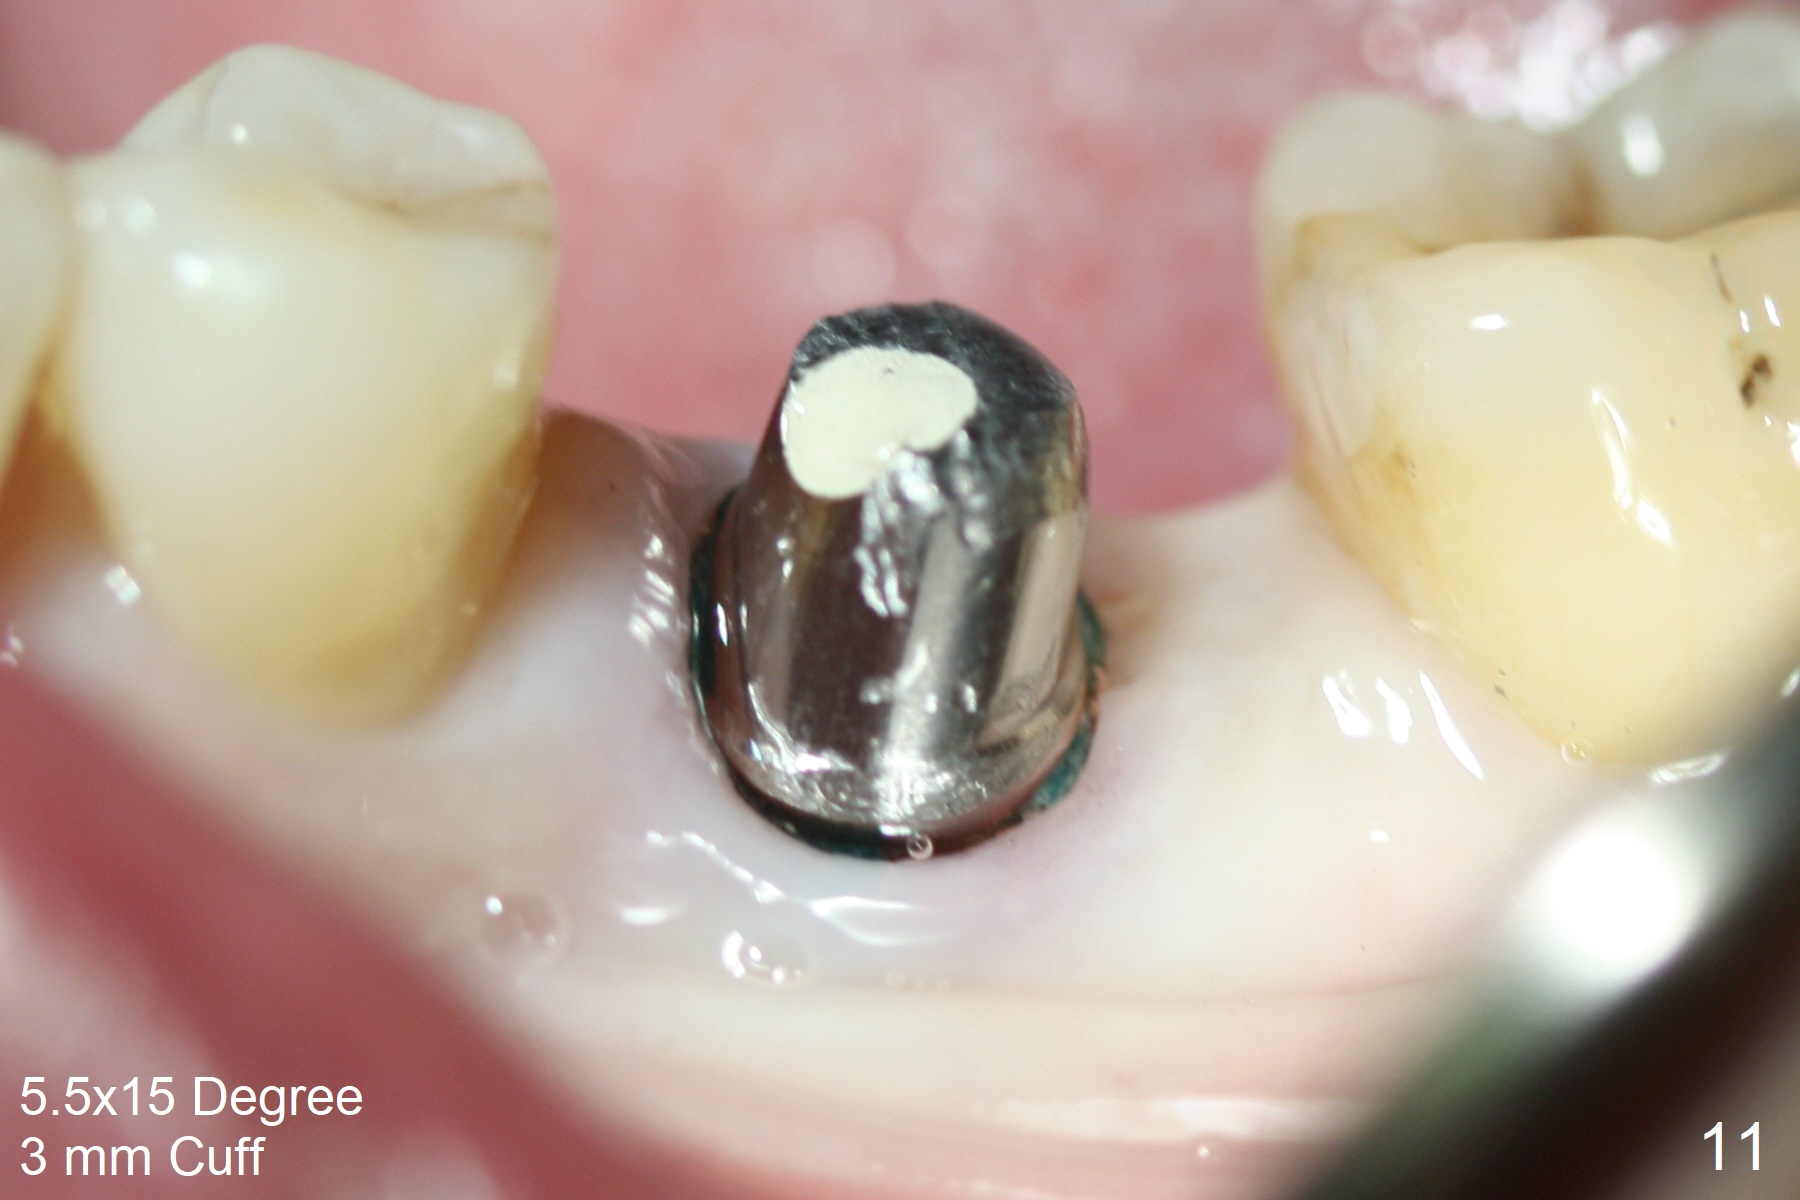

When the patient returns 9 months later, there is severe buccal gingival recession and abscess at #19 (Fig.1 *) with large mesial periradicular radiolucency (Fig.2 *). The septum is thin and the buccal crest is low after extraction (Fig.3 * (mesial root vertical fracture)). Osteotomy is initiated in the mesial socket immediately against the septum (Fig.4.5) with ~ 5 mm in the native bone. Due to severe buccal plate resorption, a shorter implant is placed (Fig.6; 5x15 mm in stead of 18 mm). There is at least 2 mm gap buccally for Vanilla Graft, which is also placed next to the implant and the neighboring root (Fig.7 *). There is clearance from the Inferior Alveolar Canal (Fig.8 red dashed line). Both the mesial and distal sockets heal 5.5 months postop (Fig.9), although the apical portion of the distal socket was not filled with allograft (Fig.7). The implant was placed mesial. The straight abutment (6.5x4(4) mm) (Fig.10) is changed to an angled one (5.5 x15 degrees 3 mm cuff (Fig.11)) before impression. The implant is also placed buccally. Therefore the implant position is far more important than its length. The abutment is retightened 2.5 months post cementation, which is related to mesiobuccal placement of the implant (Fig.12). An ideal trajectory is determined by drawing 2 horizontal lines (at crestal and apical levels: red lines in Fig.13), finding a central point of each line (vertical short line) and joining these 2 central points (Fig.14 pink line). In fact the ideal osteotomy should have been established distal to the septum in this case. Guided surgery may alleviate the issue. The crown is not loose, but the patient feels that the implant tooth cannot sustain mastication. In fact the screw is removed with hand driver (not wrench). The abutment hex is rounded and worn. A new 5.5x4(4) mm abutment is placed (without knowledge of previous use of an angled abutment) with mesial reduction to reduce undercut and buccodistal margin lowered to reduce gingival embrasure. It is that the straight abutment could decrease the chance of screw loosening. Otherwise the implant has to be removed for better trajectory.